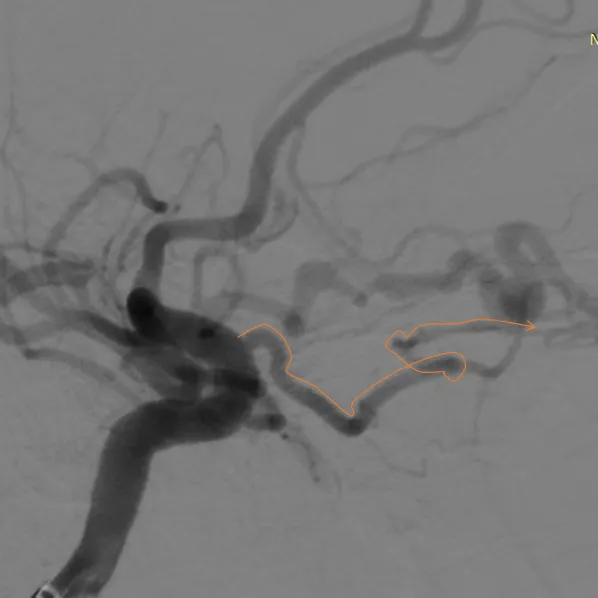

经右眼动脉工作路径

SONIC微导管到位后,手推造影确认

SONIC微导管造影证实

首次注胶

首次注胶后造影仍见瘘口区显影

继续注胶,见部分反流,停顿

停顿等待后继续注胶

造影显示瘘口消失